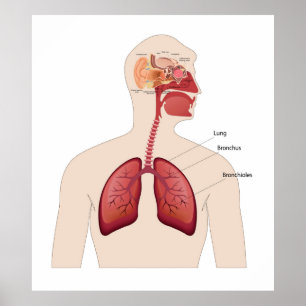

Human Yta Anatomy Relation till organ Poster

Pris258,00 kr

Human Yta Anatomy Relation till organ Poster

Pris258,00 kr